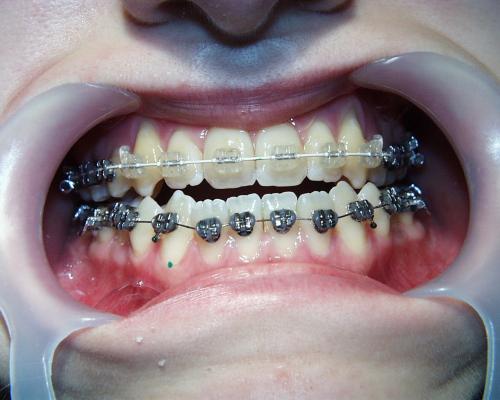

Während der Behandlung

Linkes Bild kurz vor, rechtes Bild kurz nach der Operation. Häufig ist noch eine weitere Anpassung der Zahnbögen und eine Feineinstellung der Verzahnung notwendig. In der Regel müssen die Patienten zwischen den Zahnreihen kleine Gummiringe einhängen, um die Kiefer in der gewünschten Position zu halten.